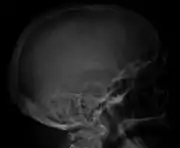

Bone pain affects almost 70% of people with multiple myeloma and is one of the most common symptoms.[2]:653[22] Myeloma bone pain usually involves the spine and ribs, and worsens with activity. Persistent, localized pain may indicate a pathological bone fracture. Involvement of the vertebrae may lead to spinal cord compression or kyphosis. Myeloma bone disease is due to the overexpression of receptor activator for nuclear factor κ B ligand (RANKL) by bone marrow stroma. RANKL activates osteoclasts, which resorb bone. The resultant bone lesions are lytic (cause breakdown) in nature, and are best seen in plain radiographs, which may show "punched-out" resorptive lesions (including the "raindrop" appearance of the skull on radiography). The breakdown of bone also leads to the release of calcium ions into the blood, leading to hypercalcemia and its associated symptoms.[23]

The diagnostic examination of a person with suspected multiple myeloma typically includes a skeletal survey. This is a series of X-rays of the skull, axial skeleton, and proximal long bones. Myeloma activity sometimes appears as "lytic lesions" (with local disappearance of normal bone due to resorption) or as "punched-out lesions" on the skull X-ray ("raindrop skull"). Lesions may also be sclerotic, which is seen as radiodense.[70] Overall, the radiodensity of myeloma is between −30 and 120 Hounsfield units (HU).[71] Magnetic resonance imaging is more sensitive than simple X-rays in the detection of lytic lesions, and may supersede a skeletal survey, especially when vertebral disease is suspected. Occasionally, a CT scan is performed to measure the size of soft-tissue plasmacytomas. Nuclear Medicine Bone scans are typically not of any additional value in the workup of people with myeloma (no new bone formation; lytic lesions not well visualized on nuclear bone scan).